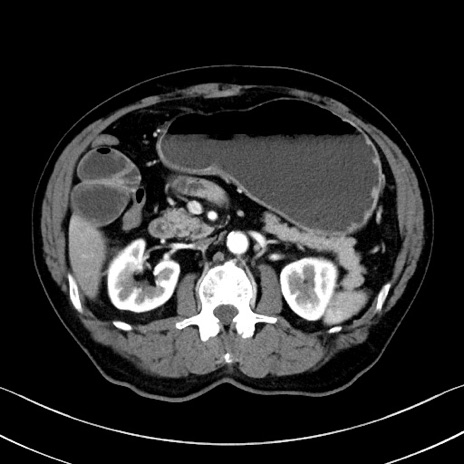

症例35(横断像)

【症例】70歳代 男性

【主訴】腹部膨満、嘔吐

【現病歴】昨日より腹部膨満感出現。本日増悪し、仙痛出現。嘔吐あり、受診。

【既往歴】糖尿病、胆摘後

【身体所見】BP 149/80mmHg、HR 74/min、BT 35.9℃、腹部:膨満、軟、圧痛なし。腸雑音減弱あり。上腹部正中切開瘢痕あり。

【データ】WBC 13500、CRP 1.72